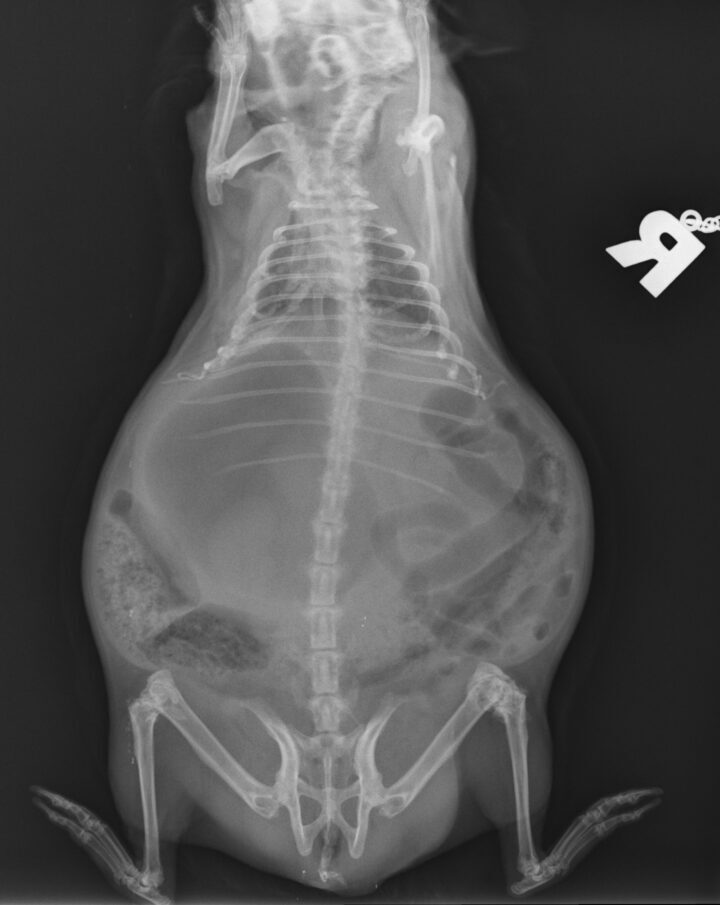

Often, clinical signs are missed, and the diagnosis in guinea pigs is made during post-mortem examination (DeCubellis and Graham, 2013). However, when present, clinical signs can range from anorexia, lethargy, tachypnoea, an absence of faecal production, cyanosis and cardiovascular shock to sudden death (DeCubellis and Graham, 2013; Edis, 2019). Patients can be presented obtunded, with palpable gastric tympany and hypothermia (Mitchell et al., 2010). It is important to distinguish this condition from bloat – another common condition in which guinea pigs present with gastric tympany.

GDV is an emergency presentation that must be identified quickly. The gaseous distension of the stomach causes it to twist on its axis at the mesentery, resulting in compression of the gastric vessels and secondary ischaemia (Edis, 2019). Fermentation of ingesta contributes to further gaseous distension in the stomach that cannot escape as the gastric outflow is also obstructed due to the twisting of the stomach.

Diagnosis is often by radiography, which should be performed following administration of analgesia and sedation if required. Radiographs show severe gaseous distension of the stomach, often taking up 50 percent of the abdominal cavity (Huynh and Pignon, 2013). In some cases, the bowel can be visualised cranial to the stomach (Mitchell et al., 2010) (Figure 5). It is important to note that the classic “double bubble” seen in cases of GDV in canine patients is not always seen radiographically, and diagnosis of GDV in guinea pigs should not be ruled out based on the absence of this sign.